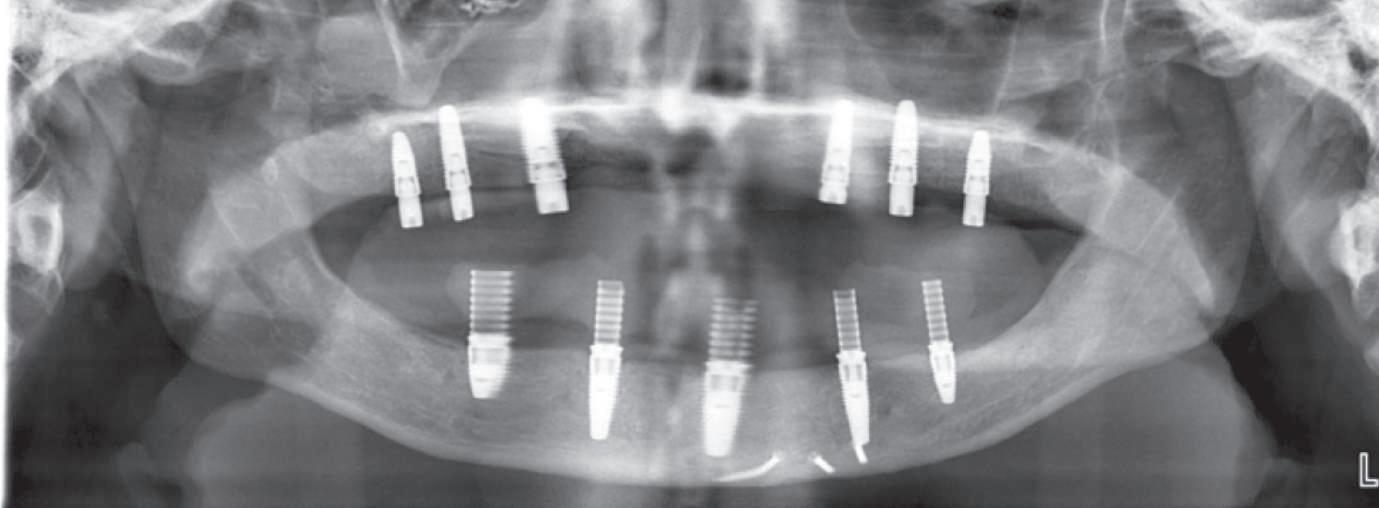

Reabilitările implantare complexe pot include abordări în etape, implicând de obicei extracţia seriată a dinţilor irecuperabili. Se evită astfel necesitatea protezelor mobilizabile prin menţinerea dinţilor naturali în cursul vindecării şi împiedică încărcarea imediată a implanturilor plasate în osul grefat. Un dezavantaj major constă în recesia gingivală. Acest articol dezbate diverse abordări pentru gestionarea modificărilor gingivale şi sugerează modificări de protocol în cursul fazei de planificare terapeutică cu implanturi.

Deşi poate varia de la pacient la altul, acest tip de tratament implică de obicei stadii multiple de inserare a implanturilor în cursul cărora dinţii reziduali dar irecuperabili sunt menţinuţi ca bonturi temporare pentru a susţine restaurări provizorii fixe. Odată cu realizarea conexiunii dintre bonturi şi primul set de implanturi, dinţii reziduali se extrag şi se efectuează o a doua etapă de inserţie a implanturilor. După vindecarea celui de-al doilea set sau a setului final de implanturi, se pot realiza procedurile protetice pe implanturi pentru a finaliza terapia. Cavallaro & Greenstein au împărţit acest protocol în două clasificări: clasa I, cu toate implanturile inserate în cursul primei etape chirurgicale; şi clasa a II-a cu două sau mai multe etape de inserare a implanturilor pentru a genera suficientă susţinere implantară.

durata tratamentului şi implicarea mai multor etape chirurgicale. Avantajele sunt numeroase, incluzând: abilitatea de a utiliza o restaurare provizorie fixă pe toată durata tratamentului şi a fazelor de vindecare, ghidajul simplificat pentru inserarea implanturilor, menţinerea funcţiei masticatorii şi managementul ţesutului moale. În pofida progreselor precum planificarea virtuală, încărcarea imediată şi suprafeţele îmbunătăţite ale corpurilor implantare, vindecarea ţesutului moale nu este încă predictibilă în mod curent. Deşi pierderea de până la 1mm din osul marginal în cursul primului an după conexiunea bontului era acceptabilă odinioară, a devenit evident că aceasta poate însemna totodată pierderea de ţesut moale în aceeaşi perioadă sau în anii următori. Indiferent că pierderea tisulară este imediată sau ulterioară, succesul tratamentului este judecat din prisma funcţiei şi a esteticii dentare dar şi a ţesutului moale.

Pacientul prezenta dentiţie maxilară şi mandibulară eşuată datorită cariei secundare provocată de xerostomia post-iradiere. Pacientul suferise o disecţie cervicală radicală pentru înlăturarea carcinomului cu celule scuamoase la nivelul gâtului cu 9 ani înainte, urmată de radioterapie dar fără limită de ecranare. S-a utilizat o abordare stadializată pentru a evita protezele mobilizabile pe ţesuturile moi, extrem de uscate. Pacientul a optat pentru tratarea prioritară la nivel mandibular.

Fig. 9 prezintă bonturile de vindecare adiacente dinţilor naturali menţinuţi temporar, iar fig. 10 bonturile individualizate din prima etapă, inserate cu un contur gingival relativ bun şi fără recesie. Recesia era clar vizibilă în jurul tuturor bonturilor din prima etapă, după extracţiile adiacente şi plasarea implanturilor din a doua etapă (fig. 11). Atitudine: S-a decis îndepărtarea acestor bonturi şi amprenta corpului implantar al tuturor implanturilor astfel încât bonturile noi şi cele din prima etapă să fie frezate împreună pentru paralelism şi poziţionarea adecvată a marginii gingivale. Întrucât aceasta necesita îndepărtarea bonturilor din prima etapă care menţineau proteza provizorie, înainte de îndepărtarea tuturor bonturilor individualizate s-au plasat bonturi provizorii, cu scopul de a asigura poziţionarea adecvată şi dimensiunea verticală a restaurării provizorii. Aceste bonturi provizorii au menţinut apoi restaurarea temporară,

Cazul (3): Refrezarea bonturilor individualizate

Figurile

9. Bonturile de vindecare.

10. Bonturile individualizate în prima etapă.

11. Recesia evidentă în jurul bonturilor din prima etapă, după extracţiile adiacente şi inserarea implanturilor din faza a doua.

12. Bonturile refrezate şi noile bonturi individualizate.

în timp ce toate bonturile individualizate au fost fabricate şi/sau frezate în laborator. Fig. 12 prezintă plasarea bonturilor refrezate (la implanturile din prima etapă) şi bonturile individualizate noi (la cele din a doua etapă).